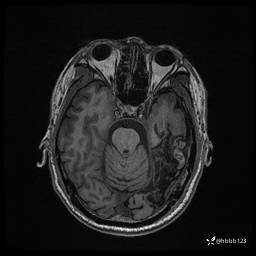

入院完善脑癫痫组合序列:

DWI:

T2 Flair: